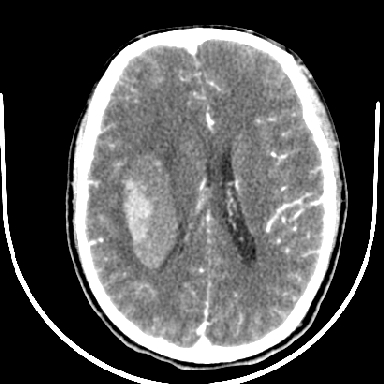

考虑高血压性脑出血,依据:

1是高血压性脑出血的好发部位,形态呈肾形,是高血压性脑出血的常见形状

2增强时占位效应加重了,考虑出血还没有停止

3病灶周围水肿不是太厉害,一般肿瘤出血水肿多非常明显

4病灶周围的‘软组织’影没有明显的强化

5至于脑血管畸形引起的出血,暂时没有看到明显的畸形血管影,也不太支持

支持右侧基底节脑出血

右侧基底节区脑出血.

支持右侧基底节区(主要为外囊区)原发性脑出血。

另附部分资料:“血液溢出血管外形成血肿,其内含有大量血红蛋白、血浆白蛋白,球蛋白,因这些蛋白对x线的吸收系数高于脑质,故ct呈现高密度阴影,ct值达40~90h,最初高密度灶呈非均匀一致性,中心密度更高,新鲜出血灶边缘不清。基底节区血肿多为“肾”型,内侧凹陷,外侧膨隆,因外侧裂阻力较小,故向外凸,其它部位血肿多呈尖圆形或不规则形”

术中抽出40ml陈旧血液,血肿底部似见一条索血管影